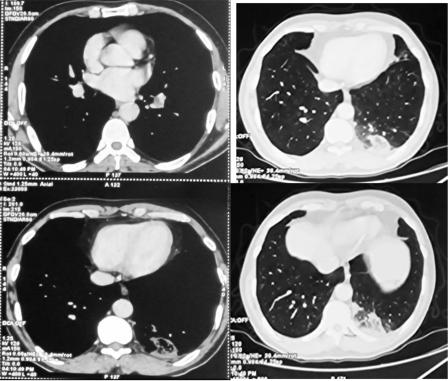

Mesenchymal Hamartoma of the Liver (MHL) is a rare benign hepatic pediatric tumor of infancy with approximately 20% of cases diagnosed during the neonatal period, typically presenting as an enlarging abdominal mass. Rare acute complications such as intralesional bleeding and infection can lead…...